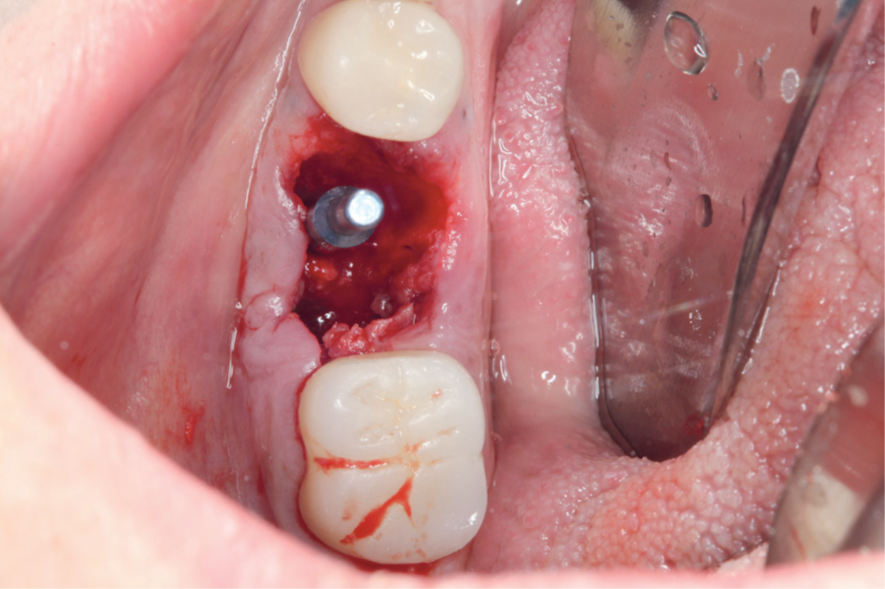

Para a instalação do implante imediato de corpo cônico cone-morse (Maestro, 4 mm x 9 mm, Implacil De Bortoli – São Paulo, Brasil), iniciou-se a fresagem de 9 mm com a fresa lança helicoidal 2.0, seguindo com a fresa cônica 3,5 mm x 9 mm com inclinação para mesial, na região mais centralizada entre a vestibular e a lingual do septo inter-radicular. Com o uso do Túnel Check Cônico 4.0 – instrumental que permite realizar a medição da profundidade da fresagem e sua inclinação –, verificou-se o paralelismo da perfuração para inserção do implante dentário (Figura 4). Em seguida, o implante dentário foi inserido com travamento final de 20 Ncm e recebeu o parafuso de cobertura correspondente (Figuras 5 e 6).